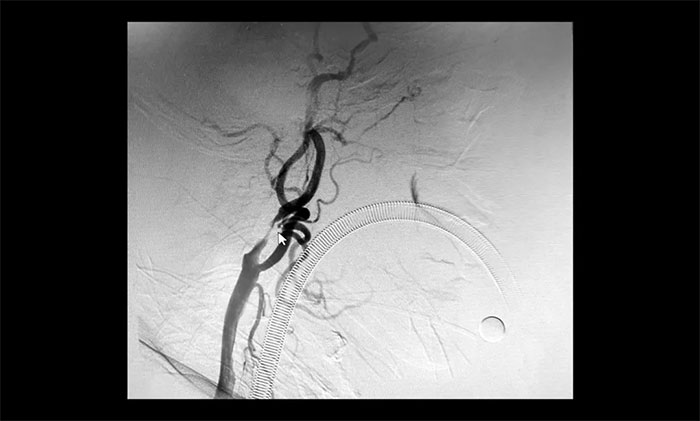

颈内动脉狭窄可分为轻度(<50%),中度(50%~69%)和重度(70%~99%),椎动脉狭窄的判别标准与之相仿。DSA检查示:患者双侧颈内动脉及左侧椎动脉存在重度狭窄,狭窄程度达到甚至超过90%,病情十分严重,遂立即收治入院。

▲ 双侧颈内动脉及左侧椎动脉重度狭窄